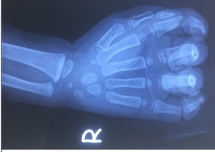

Bé gái 23 tháng tuổi nhập viện trong tình trạng nhiều vết thương bàn tay phải, trong đó đứt gần rời ngón tay số 5 do bị kẹt tay vào dây curoa máy rửa xe.